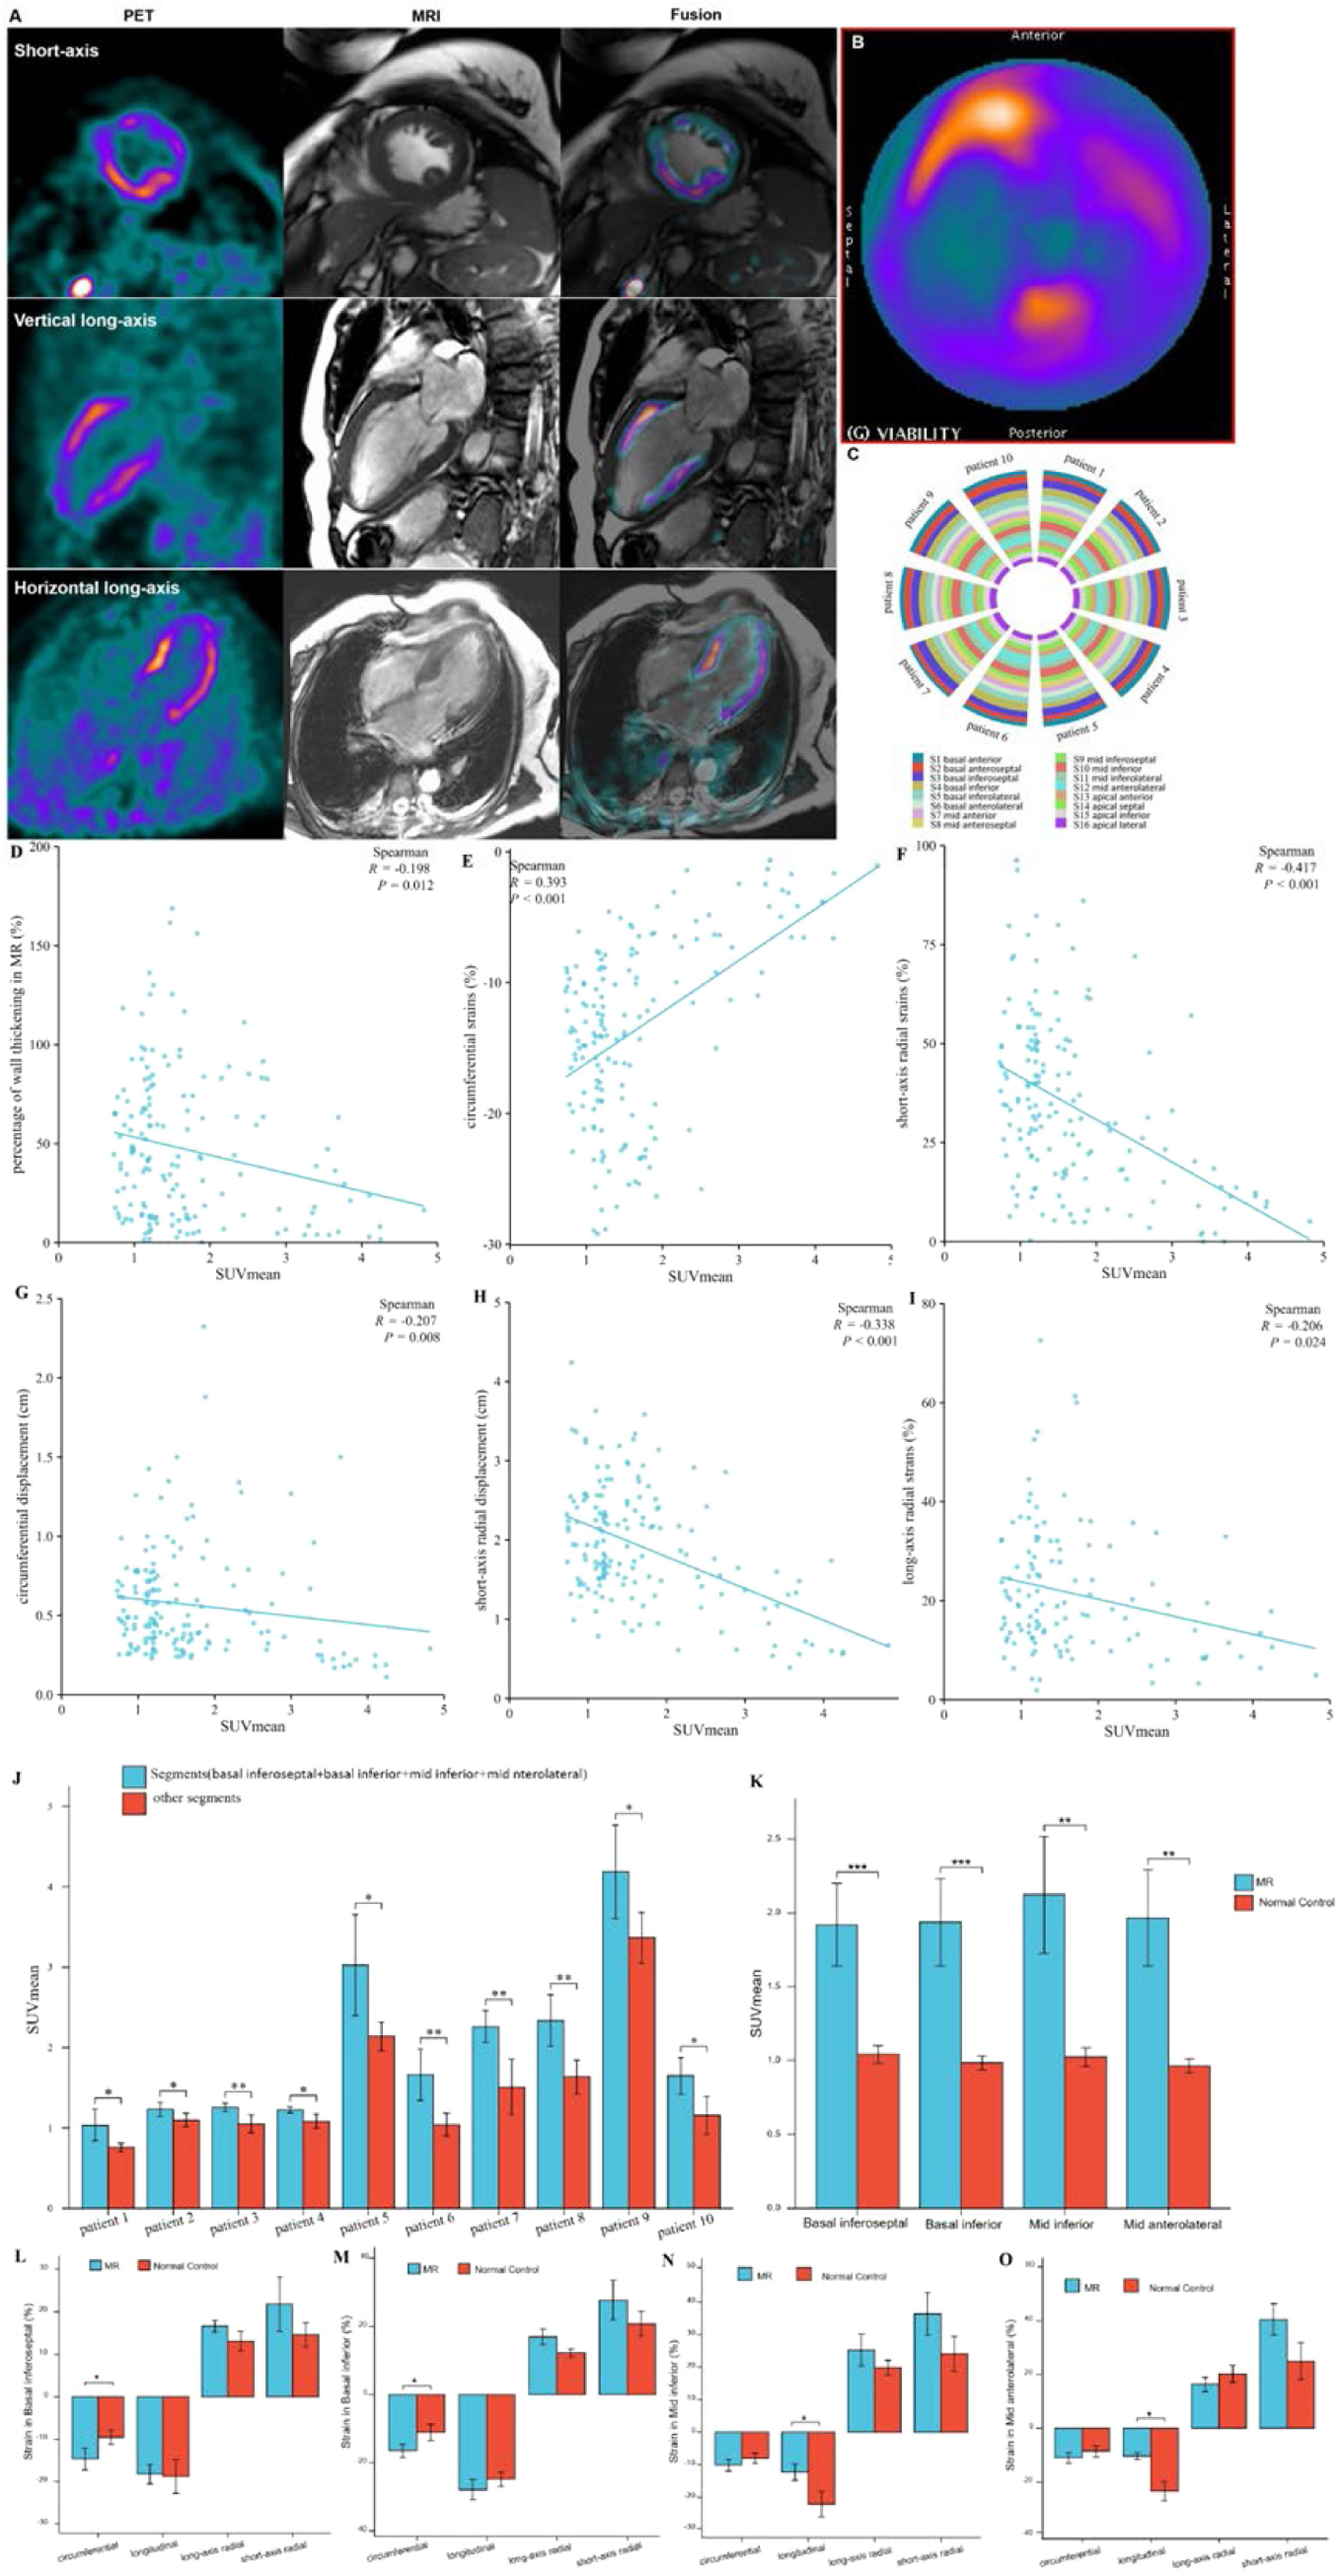

Distributions of FAPI uptake in patients with DMVRThe results from the polar map of cardiac PET images from the patients with DMVR indicated that the distribution of FAPI uptake was multifocal and irregular in the myocardial segments, with no significant differences in FAPI uptake (SUVmean) between individual myocardial segments (Fig. 5A‒C). However, for each DMVR patient, the sum of the SUVmean of FAPI uptake within segments attached to the annulus of the mitral valve and papillary muscles (basal inferoseptal, basal inferior, mid inferior, and mid anterolateral walls) was significantly higher than that in the other myocardial segments (p ˂ 0.05) (Fig. 5D). Moreover, comparison between patients with DMVR and controls revealed significantly higher FAPI-uptake (SUVmean) in the basal inferoseptal, basal inferior, mid inferior, and mid anterolateral wall segments of individuals with DMVR (1.92 ± 0.28 vs. 1.04 ± 0.06 in the basal inferoseptal wall, 1.94 ± 0.30 vs. 0.98 ± 0.05 in the basal inferior wall, 2.12 ± 0.39 vs. 1.02 ± 0.21 in the mid inferior wall, and 1.97 ± 0.33 vs. 0.96±0.05 in the mid anterolateral wall; all p < 0.01; Fig. 5E).

Images in a 63-year-old man with Mitral Valve Regurgitation (MVR) (A and B). 18F-AlF-FAPI PET images, MR images, and PET/MR fusion images in short-axis, vertical long-axis, and horizontal long-axis cine (A). The distribution of FAPI uptake in the polar map of PET images (B). There were higher FAPI uptakes in the middle myocardium, especially in the mid anterior, mid inferior and mid anterolateral wall. The uptakes of FAPI in each myocardial segment in the polar map of PET images from all participants with MVR (C). The value of SUVmean of FAPI-uptakes in each segment was represented by the width of each color bar. It showed that for each participant with MVR, there were no significant differences in FAPI-uptakes between each myocardial segment. The comparison of SUVmean between two parts of all myocardial segments in each participant with MVR (D). In each participant, SUVmean of FAPI uptakes in the part of myocardial segments, including basal inferoseptal, basal inferior, mid inferior and mid anterolateral wall, was higher than that in the other part including the remaining myocardial segments. The comparison of SUVmean in the basal inferoseptal, basal inferior, mid inferior and mid anterolateral wall between all participants with MR and normal ones (E). There was significant differences in SUVmean of each myocardial segments between them. The correlation analysis between percentage of wall thickening and SUVmean in the all myocardial segments from MVR participants (F). The correlation analysis between the peak circumferential, short and long-axis radial strains and displacements and SUVmean in the all myocardial segments from MVR participants (G‒K). The comparison of the peak circumferential, longitudinal, long-axis radial and short-axis radial strains in the basal inferoseptal (L), basal inferior (M), mid inferior (N) and mid anterolateral wall (O) between all participants with MR and normal ones. Each column represents mean ± SD. Asterisks indicate significant differences between them. *p < 0.05, **p < 0.01, ***p < 0.001.

Analysis of short-axis CMR polar maps revealed a significant negative correlation between the percentage of systolic LV wall thickening and FAPI uptake (SUVmean) in all myocardial segments of DMVR patients (r = -0.198, p = 0.012; Fig. 5F). Moreover, the peak circumferential and short-axis radial strains and displacement of the corresponding orientation in all myocardial segments were inversely correlated with FAPI (SUVmean). The results were as follows: peak circumferential and short-axis radial strains, r = 0.393, p < 0.001 and r = -0.417, p < 0.001, and circumferential and short-axis radial displacement, r = -0.207, p = 0.008 and r = -0.338, p < 0.001 (Fig. 5G‒J). Although the peak long-axis radial strains in all myocardial segments were inversely correlated with the SUVmean of FAPI (r = -0.206, p = 0.024), no significant correlation was observed between the long-axis radial displacement and SUVmean of FAPI (Fig. 5K).

In addition, data from the basal inferoseptal, basal inferior, mid inferior and mid anterolateral walls from the short-axis view of CMR images revealed significant differences in the peak circumferential strains in both the basal inferoseptal and basal inferior walls between patients with DMVR and healthy controls (-14.74 ± 2.55 vs. -9.58 ± 1.66 and -16.51 ± 1.96 vs. -11.11 ± 2.35; all p < 0.05). Comparison between DMVR patients and controls revealed significantly lower peak longitudinal strains in both the mid inferior (-12.24 ± 2.50 vs. -22.10 ± 3.92) and mid anterolateral wall segments of DMVR patients (-10.33 ± 1.36 vs. -23.30 ± 3.59; p < 0.05; Fig. 5L‒O).